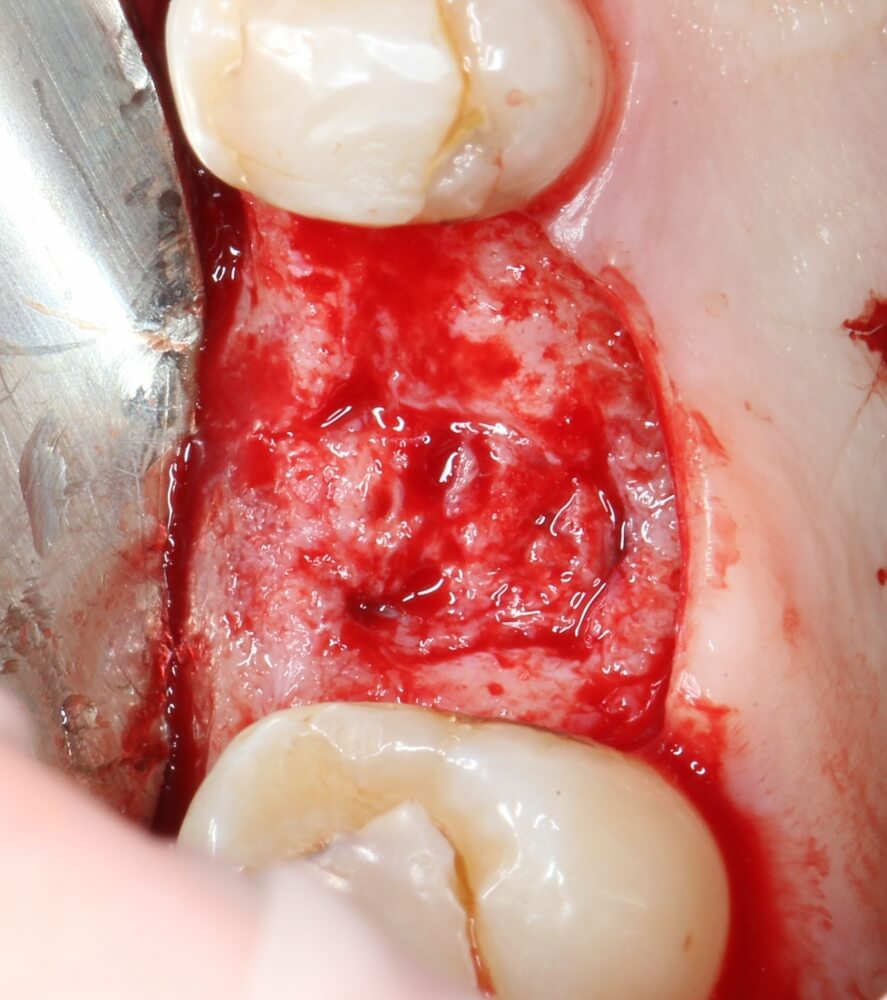

Кортикальная фреза погружается строго до отметки (см выше). В нашем клиническом случае (с синуслифтингом) это особенно важно, чтобы имплантат не улетел в субантральное пространство. Таким образом получаем лунку, полностью конгруэнтную будущему имплантату. Это очень-очень важно:

Пришло время вернуться к синуслифтингу и заполнить сформированное ранее субантральное пространство графтом (Geistlich Bio-Oss Pen):

запечатываем заполненное субантральное пространство: